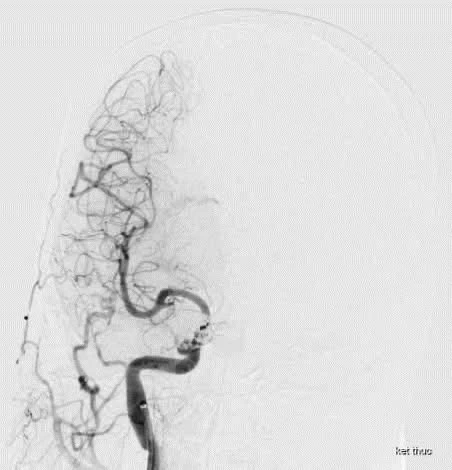

Bác sĩ thực hiện các xét nghiệm bao gồm chụp CT mạch máu não và chụp mạch máu số hóa xóa nền (DSA). Ảnh: BVCC

Sau khi thăm khám, thực hiện các xét nghiệm bao gồm chụp CT mạch máu não và chụp mạch máu số hóa xóa nền (DSA), bệnh nhân được chẩn đoán bị rò động mạch cảnh – xoang hang (Carotid-Cavernous Fistula - CCF).

Bệnh nhân được chẩn đoán bị rò động mạch cảnh – xoang hang. Ảnh: BVCC